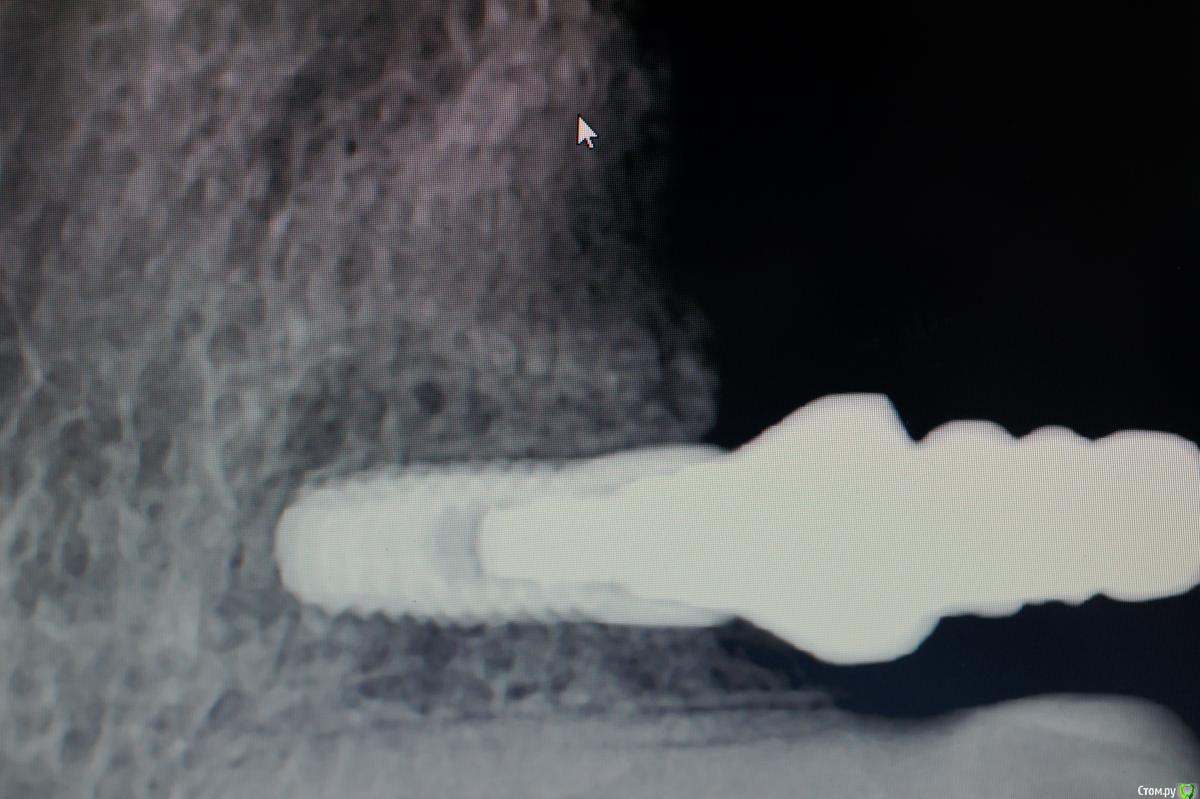

Des Опубликовано 22 мая, 2015 Поделиться Опубликовано 22 мая, 2015 Проблема с припасовкой каркаса при протезировании на имплантах (система Имплантиум): - каркас уходит язычноСлепочные трансферы для закрытой ложки установленыСлепок снят методом закрытой ложки А-силиконом i-Sil, шахты трансферов изолированы воском; аналоги имплантов подобраны правильно, но в слепок их устанавливал техник без моего контроля; на модели каркас установлен адекватно, аббатменты установлены в аналоги на модели правильно Вопрос: есть ли мнения на счет того, на каком этапе допущена ошибка?Мои предположения: либо искажения на этапе снятия слепка, либо техник неправильно поставил трансферы в слепок. Ссылка на комментарий

Des Опубликовано 22 мая, 2015 Автор Поделиться Опубликовано 22 мая, 2015 абатмент разные: 5.5 на импланте в области 4 зуба и 6.5 - в области 6-ого, Evgen-Vozhd правильно посоветовал сделать модель по старому оттиску, но к сожалению оттиск утилизирован, хороший урок на будущее Ссылка на комментарий

Юрьевич Опубликовано 22 мая, 2015 Поделиться Опубликовано 22 мая, 2015 Я думаю что это недостаток,что трансферы устанавливаются обратно в слепок и нет гарантии точной посадки.Может быть методика закрытой ложки применяется для одиночек? Ссылка на комментарий

Юрьевич Опубликовано 22 мая, 2015 Поделиться Опубликовано 22 мая, 2015 (изменено) Я нашёл в каталоге прикручиваемые трансферы,какая у них гарантия точности установки обратно в слепок? Изменено 22 мая, 2015 пользователем Юрьевич Ссылка на комментарий